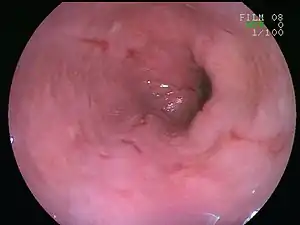

![]() | |

| An esophageal ulcer visualized by esophagoscopy: the reddened area at 10 o'clock on the surface of the mucosa. | |

Esophagitis can be diagnosed by upper endoscopy, biopsy, upper GI series (or barium swallow), and laboratory tests.[5]

An upper endoscopy is a procedure to look at the esophagus by using an endoscope. While looking at the esophagus, the doctor is able to take a small biopsy. The biopsy can be used to confirm inflammation of the esophagus.